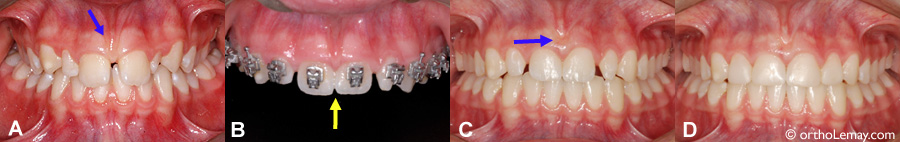

(A) Frein labial (flèche) associé à un diastème entre les centrales supérieures.

(B) L’espace entre les centrales a tout d’abord été fermé en orthodontie.

(C) Résultat à la fin du traitement et après une frénectomie. Les espaces restants sont dûs à des latérales étroites.

(D) Les latérales ont été élargies par le dentiste, ce qui contribuera à la stabilité de l’espace fermé.